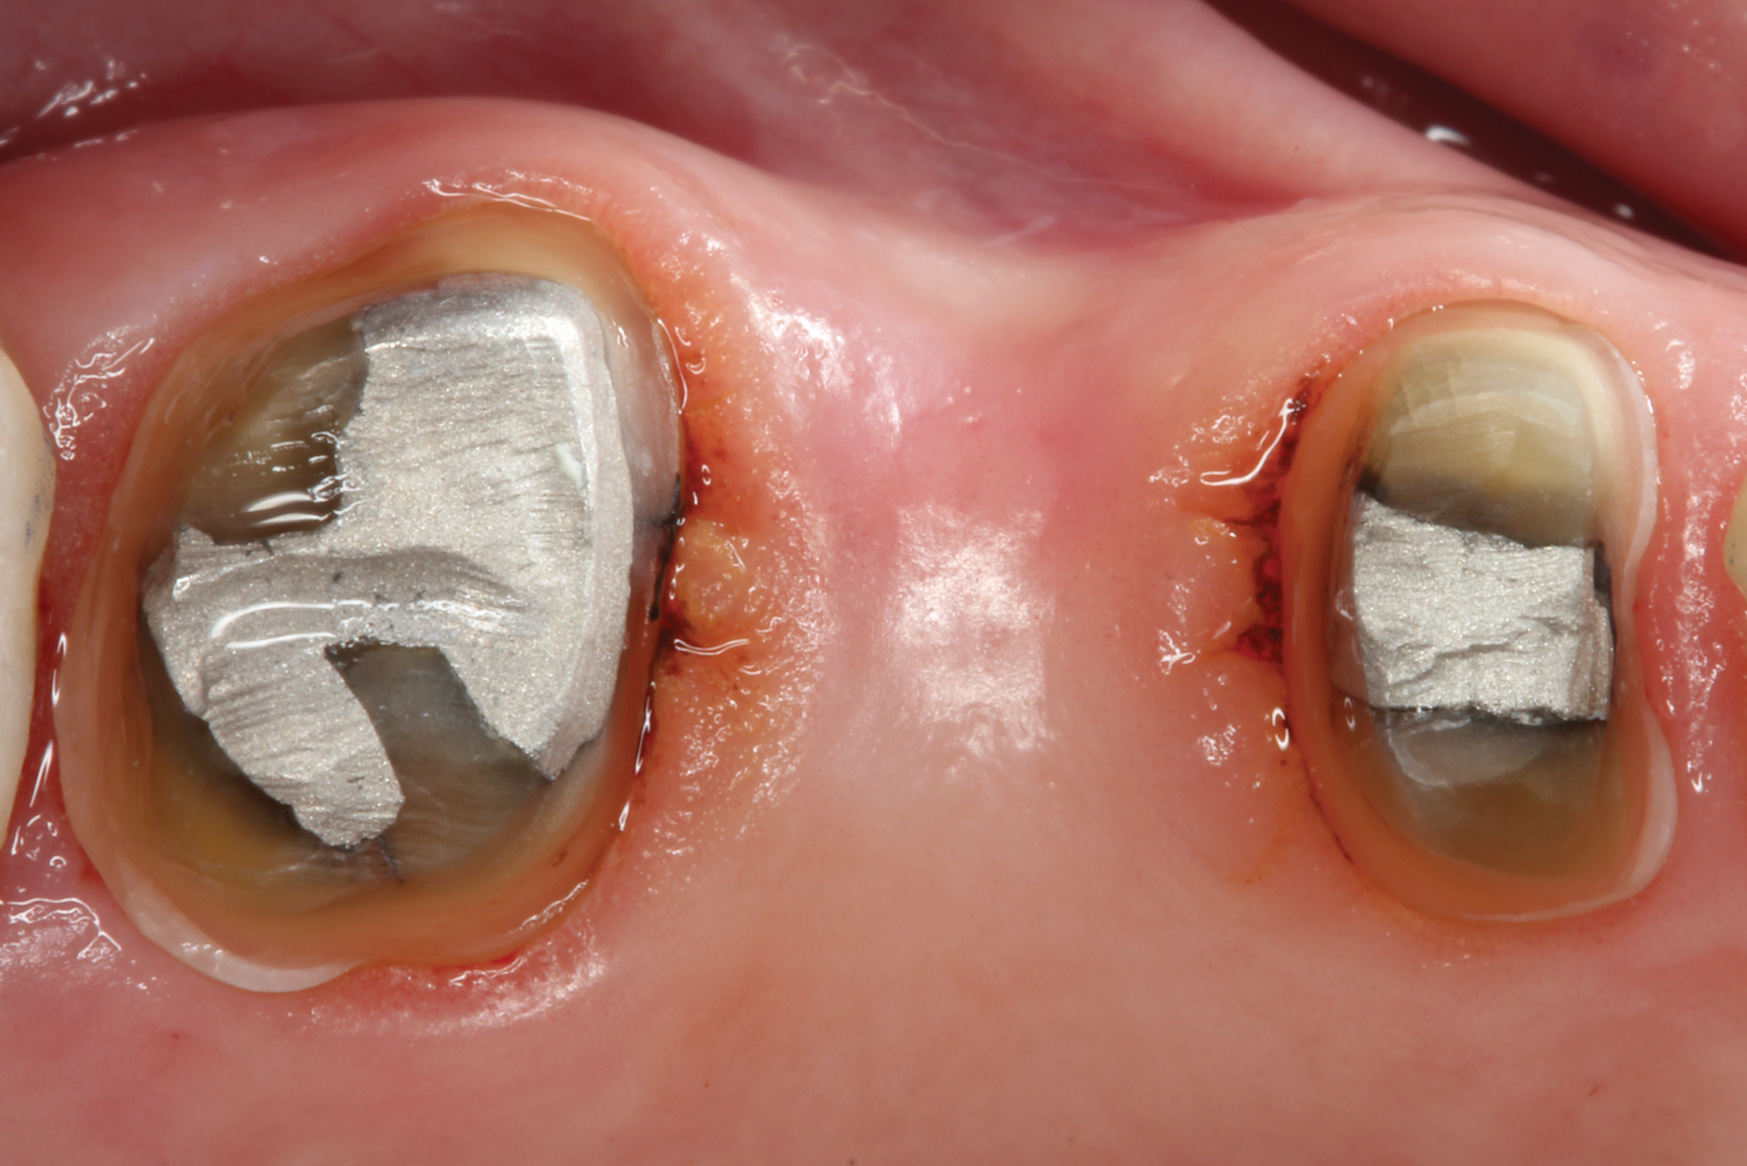

With these limitations acknowledged, visual inspection of tooth preparations after air abrasion reveals that this modality is effective in removing remnant restorative materials, stains, and temporary cement, leaving a clean, matte surface for bonding (Figure 11 through Figure 14). Air abrasion also can smooth the internal aspects of a cavity preparation to help enable better adaptation of the restorative material (Figure 15 and Figure 16). The technique-sensitive nature of adhesive bonding may justify this extra procedure to ensure a clean, smooth preparation.

Fig 13. Crown preparations with temporary cement remnants prior to air abrasion (Fig 13) and after air abrasion (Fig 14) (case by Mohammed Badahman, DDS).

Figure 13

Fig 14. Crown preparations with temporary cement remnants prior to air abrasion (Fig 13) and after air abrasion (Fig 14) (case by Mohammed Badahman, DDS).

Figure 14